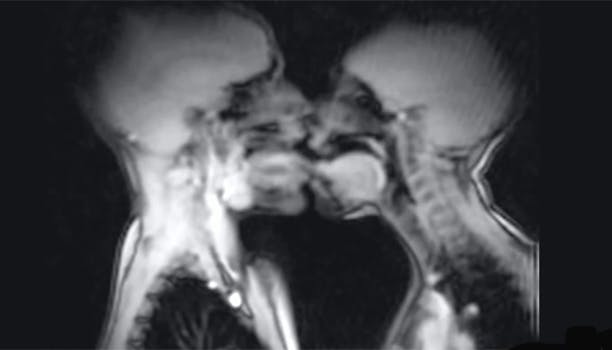

Det ér da fascinerende, er det ikke?!! Se med her: